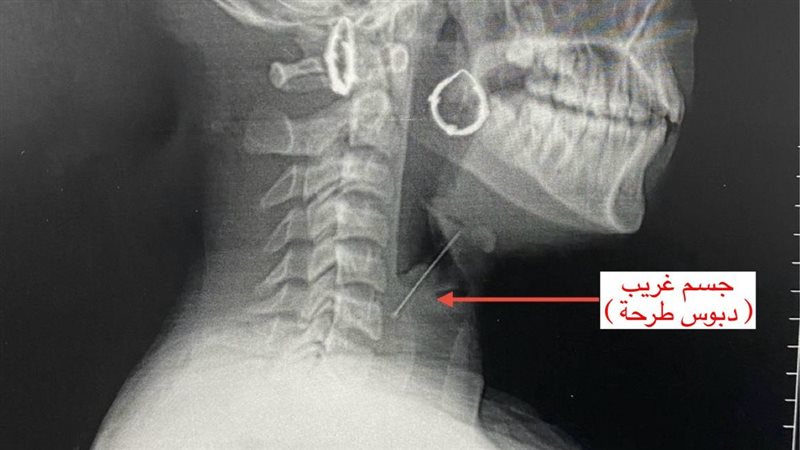

واستقبل قسم الاستقبال والطوارئ بالمستشفى المريضة وهي تعاني من آلام شديدة بالرقبة وصعوبة حادة في التنفس، حيث جرى على الفور إجراء الفحوصات والأشعة اللازمة التي كشفت عن استقرار الدبوس فى منطقة دقيقة بمدخل مجرى التنفس، ما شكّل خطورة على حياتها.